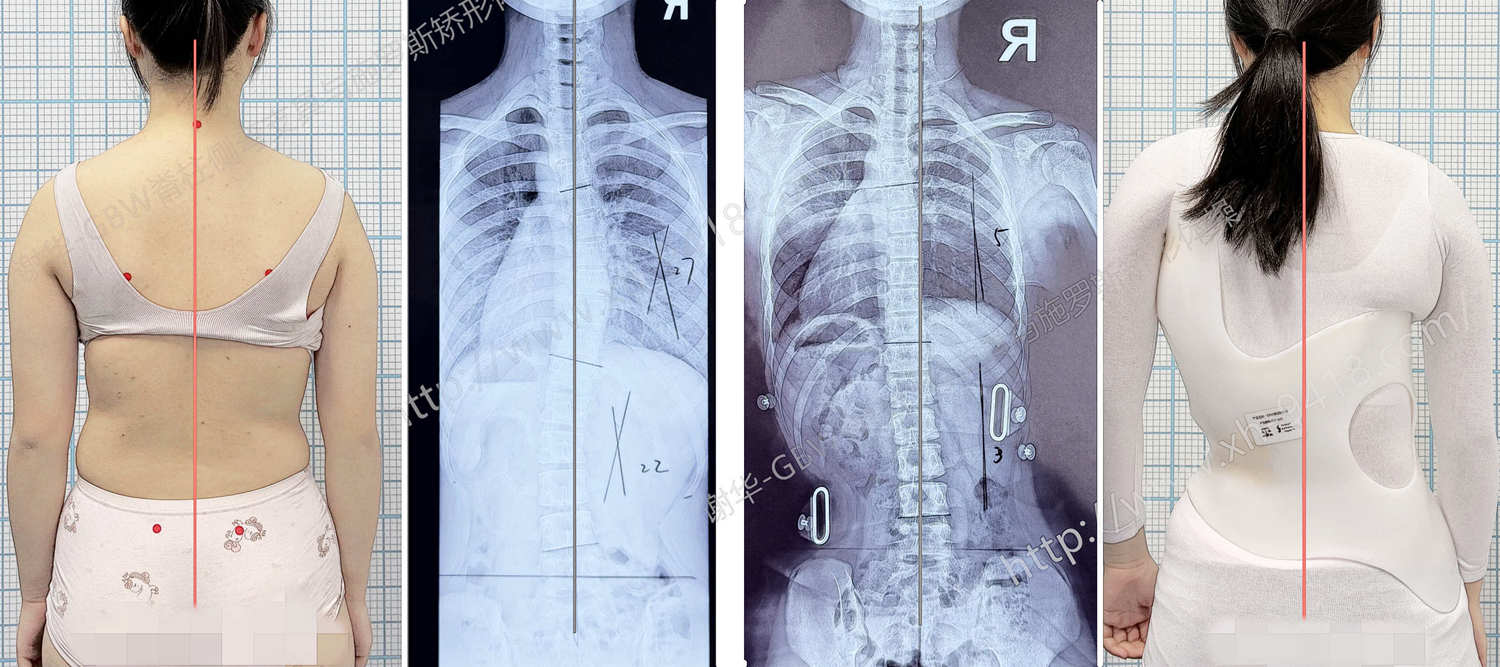

何X,女,12岁6个月。半年前发现脊柱侧弯,当时拍摄X线片显示脊柱呈 S形的侧弯曲线,Cobb角为:胸弯21°、腰弯17°。由于当时弯曲度数不大,暂时选择锻炼结合定期观察随访。

半年后复查X线片,发现侧弯曲线出现明显进展:胸弯增加至27°,腰弯增加至22°。同时骨龄评估显示 Risser征1级,提示孩子正处于生长发育的快速阶段,也是脊柱侧弯最容易进展的时期。综合评估后,建议家长为孩子定制 GBW型矫形支具 进行干预。

在家长和孩子的积极配合下,孩子坚持规范佩戴GBW支具4个月。近日来成都工作室进行复查评估:在脱支具后站立位观察,躯干体表基本恢复对称;前屈位检查时,背部剃刀背明显降低至3°。从体表姿态来看,脊柱侧弯的外观已经得到明显改善。